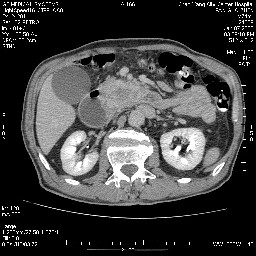

女,74岁,呕吐10余日

壶腹部的占位性病变,考虑为十二指肠癌并梗阻,但脾内多发性低密度区为转移吗?

还有胃、脾之间可见有侧支循环建立。左肾盂积水。

考虑来源于十二指肠水平段的恶性占位,侵及周围组织,特别是胰腺,可见区域淋巴结肿大,左侧下腔静脉畸形。

十二指肠水平段腔内占位伴梗阻,中等度较为均匀的强化,洗脱慢,区域淋巴结显示增多,符合腺癌表现。下腔静脉变异。

十二指肠降段扩张,水平段狭窄成鼠尾状,肠壁明显增厚,胰腺勾突增大成不均匀强化,其内可见低密度区,胆囊增大,1十二指肠水平段腺癌侵犯胰腺勾突可能大,2胰腺癌侵犯十二指肠(只有胆囊增大没有肝内外胆管扩张不好解释)代除外.

十二指肠降段扩张,水平段狭窄成鼠尾状,肠壁明显增厚,胰腺勾突增大成不均匀强化,其内可见低密度区,胆囊增大,1十二指肠水平段腺癌侵犯胰腺勾突可能大,2胰腺癌侵犯十二指肠 。

今日手术结果:胰腺钩突癌侵犯十二直肠,腹腔淋巴结转移.